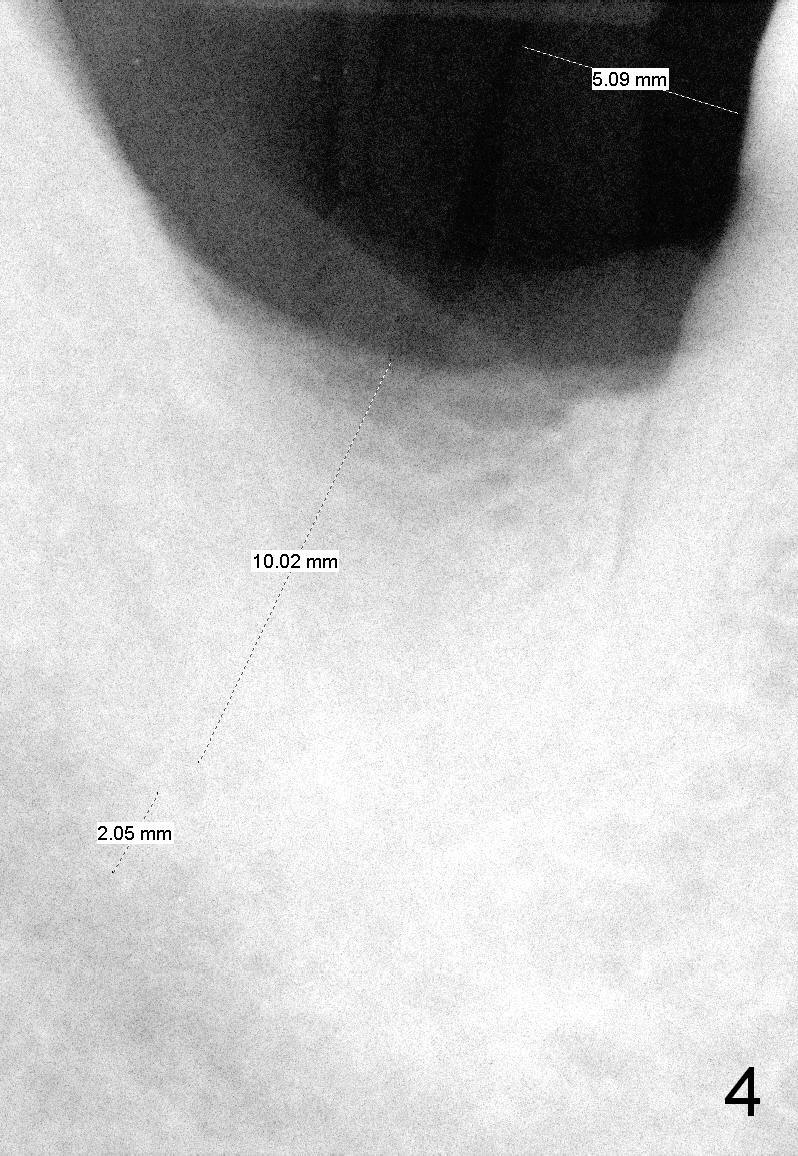

After successful immediate implant at the site of #2, he agrees to have an implant at the site of #31. The bone height has reduced to 13 mm; it appears that a 10 mm bone-level implant is appropriate (Fig.4).